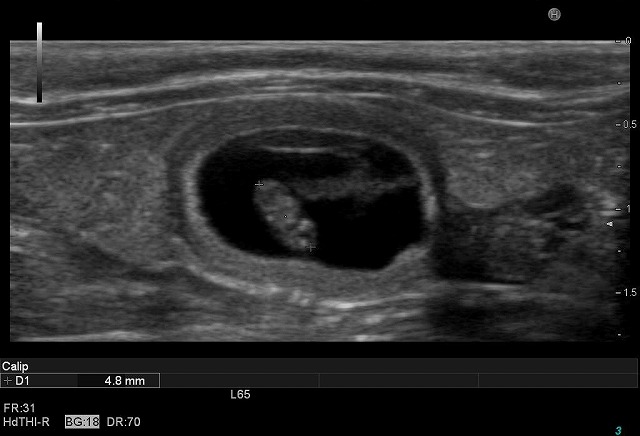

直径約10mmの子宮の中に約4mmの胎児が見えます。

20100312090335.jpg